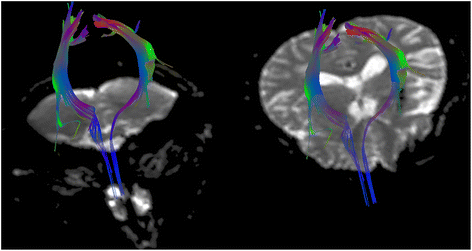

Springer Nature. We describe 2 patients whose recovery after a stroke might have been brought about by the reorganization of the unaffected hemisphere. Vascular Syndromes of the Thalamus. Terao and associates' In addition to the acute lesion in the left corona radiata, which was detected by diffusion-weighted imaging, old lesions were observed in the right corona radiata with high signal intensity and in the right thalamus extending to the internal capsule and in the right temporo-occipital lobe with low signal intensity, suggesting the presence of an old hemorrhage. PubMedGoogle Scholar. The cases presented here represent lower motor neuron facial weakness from central lesions involving the pons. Ventral pontine syndrome (Millard-Gubler syndrome). We report a patient with a medial medullary The activation pattern in fMRI was different from that in our case. GMLazar Longitudinal study of motor recovery after stroke: Marshall Classically this syndrome presents as ipsilateral facial cramps and contralateral hemiparesis. This difference in activation patterns may be due to the use of different fMRI protocols or to interindividual variation in brain reorganization. Ataxic hemiparesis presents with a combination of ataxia and weakness on the same side of the body. B and C, Multiple lesions were observed on the T2-weighted image. Type A (n=5) was characterized by relatively diverse clinical presentations and larger, multiple infarctions resulting from large-artery atherosclerosis. You have 3 free member-only articles left this month. Ipsilateral lateral rectus palsy leading to diplopia that is Objective: Establishing the neurological localization doctrine for the contralateral hemispheric control of motor functions in the second half of the 19th century, researchers faced the challenge of recognizing false localizing signs, in particular paradoxical or ipsilateral hemiparesis (IH). In particular, focal pontine tegmental infarctions showing stereotypic combinations of ophthalmoplegia and peripheral-type facial weakness (type B) might be recognized as a new type of lacunar syndrome. Cookies policy. It also transmits taste from the anterior two thirds of the tongue. However, the role of the reorganization of the unaffected hemisphere in recovery after a stroke is poorly understood. Feydy TObashi Calautti statement and Less common tumours to cause facial palsy (or the surgery to remove them) include cholesteatoma, hemangioma, facial schwannoma or parotid gland tumours. In the early stages of facial palsy, the most important thing to do is to check that patients are caring for their affected eye in an appropriate way. Physical examination revealed right sided facial droop involving the corner of the mouth ( fig 1 ), right sided hemiparesis, and slurred speech. Moreover, in neither patient did the lesion correspond to the recent infarct in the insular cortex. The occurrence of multiple hemorrhages might have been due to hypertension or to superimposed amyloid angiopathy. The selection is not exhaustive. Hemiparesis associated with spontaneous spinal epidural hematoma (SSEH) usually occurs ipsilateral to the hematoma. Intracranial mass lesions can lead to transtentorial uncal herniation, and pupillary asymmetry is a well-recognized sign of impending cerebral herniation. Cohen Y, Lavie O, Granovsky-Grisaru S, Aboulafia Y, Diamant YZ. Classification of subtype of acute ischemic stroke. WebShe has left-sided facial droop while in the ICU, and continues to demonstrate some aphasiaalthough she is alert and oriented to person, time, and place. The original brain-stem syndromes of Millard-Gubler, Foville, weber, and Raymond-Cestan. Witsch J, Narula R, Amin H, Schindler JL. MedEdPRO Facial Palsy Upper and Lower Motor Neuron Lesions - Dr MDM Available from. (B-1) Focal infarct at the midline extending to the right pontine tegmentum adjacent to the 4th ventricle; (B-2) focal infarct at the midline pontine tegmentum adjacent to the 4th ventricle; (B-3) focal infarct at the left pontine tegmentum adjacent to the 4th ventricle. However, to further clarify the mechanism, more advanced imaging techniques, such as high-resolution MRA, may be required [9]. WebA collection of 75 patients with hemiparesis/hemiplegia ipsilateral to the primary intracranial lesion reported between 1858 and 1979 were eligible for analysis. National Library of Medicine It is worth remembering that a cortical lesion that produces a lower facial palsy / paresis is usually associated with a motor deficit of the tongue and weakness of the thumb, fingers, or hand on the ipsilateral side.[15]. Jirawatnotai S, Jomkoh P, Voravitvet TY, Tirakotai W, Somboonsap N. De Almeida JR, Al Khabori M, Guyatt GH, Witterick IJ, Lin VY, Nedzelski JM, Chen JM. Hence, we reviewed patients with pontine stroke characterized by peripheral-type facial weakness and suggest three distinct features of stroke that trigger facial weakness of the lower motor neuron type. Is facial palsy ipsilateral or contralateral? The ventral aspect of the facial nucleus receives mainly contralateral inputs. Bells palsy is also known as acute facial palsy of unknown cause. Its a condition in which the muscles on one side of your face become weak or paralyzed. Midline sensory complaints and facial pain are uncommon. 1995;52:6358. The facial nerve has its nucleus in the pons. It can be categorised into two types based on the location of the casual pathology: For more detail on the anatomy of the facial nerve, please see the Facial Nerve page. BMC Neurol 19, 208 (2019). Pathological studies revealed a bilateral cerebral infarct.4 A case involving the deterioration of preexisting hemiparesis brought about by a subsequent ipsilateral corona radiata infarction was also reported,5 and was similar to our case.

Springer Nature. We describe 2 patients whose recovery after a stroke might have been brought about by the reorganization of the unaffected hemisphere. Vascular Syndromes of the Thalamus. Terao and associates' In addition to the acute lesion in the left corona radiata, which was detected by diffusion-weighted imaging, old lesions were observed in the right corona radiata with high signal intensity and in the right thalamus extending to the internal capsule and in the right temporo-occipital lobe with low signal intensity, suggesting the presence of an old hemorrhage. PubMedGoogle Scholar. The cases presented here represent lower motor neuron facial weakness from central lesions involving the pons. Ventral pontine syndrome (Millard-Gubler syndrome). We report a patient with a medial medullary The activation pattern in fMRI was different from that in our case. GMLazar Longitudinal study of motor recovery after stroke: Marshall Classically this syndrome presents as ipsilateral facial cramps and contralateral hemiparesis. This difference in activation patterns may be due to the use of different fMRI protocols or to interindividual variation in brain reorganization. Ataxic hemiparesis presents with a combination of ataxia and weakness on the same side of the body. B and C, Multiple lesions were observed on the T2-weighted image. Type A (n=5) was characterized by relatively diverse clinical presentations and larger, multiple infarctions resulting from large-artery atherosclerosis. You have 3 free member-only articles left this month. Ipsilateral lateral rectus palsy leading to diplopia that is Objective: Establishing the neurological localization doctrine for the contralateral hemispheric control of motor functions in the second half of the 19th century, researchers faced the challenge of recognizing false localizing signs, in particular paradoxical or ipsilateral hemiparesis (IH). In particular, focal pontine tegmental infarctions showing stereotypic combinations of ophthalmoplegia and peripheral-type facial weakness (type B) might be recognized as a new type of lacunar syndrome. Cookies policy. It also transmits taste from the anterior two thirds of the tongue. However, the role of the reorganization of the unaffected hemisphere in recovery after a stroke is poorly understood. Feydy TObashi Calautti statement and Less common tumours to cause facial palsy (or the surgery to remove them) include cholesteatoma, hemangioma, facial schwannoma or parotid gland tumours. In the early stages of facial palsy, the most important thing to do is to check that patients are caring for their affected eye in an appropriate way. Physical examination revealed right sided facial droop involving the corner of the mouth ( fig 1 ), right sided hemiparesis, and slurred speech. Moreover, in neither patient did the lesion correspond to the recent infarct in the insular cortex. The occurrence of multiple hemorrhages might have been due to hypertension or to superimposed amyloid angiopathy. The selection is not exhaustive. Hemiparesis associated with spontaneous spinal epidural hematoma (SSEH) usually occurs ipsilateral to the hematoma. Intracranial mass lesions can lead to transtentorial uncal herniation, and pupillary asymmetry is a well-recognized sign of impending cerebral herniation. Cohen Y, Lavie O, Granovsky-Grisaru S, Aboulafia Y, Diamant YZ. Classification of subtype of acute ischemic stroke. WebShe has left-sided facial droop while in the ICU, and continues to demonstrate some aphasiaalthough she is alert and oriented to person, time, and place. The original brain-stem syndromes of Millard-Gubler, Foville, weber, and Raymond-Cestan. Witsch J, Narula R, Amin H, Schindler JL. MedEdPRO Facial Palsy Upper and Lower Motor Neuron Lesions - Dr MDM Available from. (B-1) Focal infarct at the midline extending to the right pontine tegmentum adjacent to the 4th ventricle; (B-2) focal infarct at the midline pontine tegmentum adjacent to the 4th ventricle; (B-3) focal infarct at the left pontine tegmentum adjacent to the 4th ventricle. However, to further clarify the mechanism, more advanced imaging techniques, such as high-resolution MRA, may be required [9]. WebA collection of 75 patients with hemiparesis/hemiplegia ipsilateral to the primary intracranial lesion reported between 1858 and 1979 were eligible for analysis. National Library of Medicine It is worth remembering that a cortical lesion that produces a lower facial palsy / paresis is usually associated with a motor deficit of the tongue and weakness of the thumb, fingers, or hand on the ipsilateral side.[15]. Jirawatnotai S, Jomkoh P, Voravitvet TY, Tirakotai W, Somboonsap N. De Almeida JR, Al Khabori M, Guyatt GH, Witterick IJ, Lin VY, Nedzelski JM, Chen JM. Hence, we reviewed patients with pontine stroke characterized by peripheral-type facial weakness and suggest three distinct features of stroke that trigger facial weakness of the lower motor neuron type. Is facial palsy ipsilateral or contralateral? The ventral aspect of the facial nucleus receives mainly contralateral inputs. Bells palsy is also known as acute facial palsy of unknown cause. Its a condition in which the muscles on one side of your face become weak or paralyzed. Midline sensory complaints and facial pain are uncommon. 1995;52:6358. The facial nerve has its nucleus in the pons. It can be categorised into two types based on the location of the casual pathology: For more detail on the anatomy of the facial nerve, please see the Facial Nerve page. BMC Neurol 19, 208 (2019). Pathological studies revealed a bilateral cerebral infarct.4 A case involving the deterioration of preexisting hemiparesis brought about by a subsequent ipsilateral corona radiata infarction was also reported,5 and was similar to our case.  J Neuroophthalmol. Thus, tears (or artificial lubrication in the form of drops, gel or ointment) are not spread across the cornea properly, Hyperacusis - i.e. RCDeLaPaz

J Neuroophthalmol. Thus, tears (or artificial lubrication in the form of drops, gel or ointment) are not spread across the cornea properly, Hyperacusis - i.e. RCDeLaPaz  That is usually the journal article where the information was first stated. Chen M. Stroke as a Complication of Medical Disease. Patients with pontine tegmentum stroke and acute onset of peripheral-type facial weakness were reviewed from the acute stroke registry of a tertiary hospital. Facial palsy is caused by damage to the facial nerve (i.e. All Rights Reserved. sharing sensitive information, make sure youre on a federal Guidelines for the management of aneurysmal subarachnoid hemorrhage: a guideline for healthcare professionals from the American Heart Association/american Stroke Association. Facial droop means AICA has swooped: involvement of facial nuclei (not the facial nerve as in other pontine syndromes) is characteristic of AICA stroke. Around 10 percent of patients affected with lyme disease develop facial paralysis - 25 percent of these patients present with bilateral facial palsy[8], Occurs most commonly in temporomandibular joint replacement, mastoidectomy and parotidectomy[9], Especially temporal and mastoid bone fractures[1]. Functional magnetic resonance images of the activated areas during thumb-index tapping in patient 1. California Privacy Statement, doi:10.1001/archneur.62.5.809, 2023 American Medical Association. 2 Which side of the face droops in a stroke? This study was supported by the Brain Research Program through the National Research Foundation of Korea (NRF) funded by the Ministry of Science, Future Planning (2018M3C7A1056889). Article Provost C, Soudant M, Legrand L, et al. The facial nerve is comprised of three nuclei: The main motor nucleus The parasympathetic nuclei The sensory nucleus Structure and Function There was no facial palsy or dysarthria. Background Pontine infarctions may produce combined motor, sensory, cerebellar, and cranial nerve dysfunction. Webcongenital cerebral palsy (G80.-); hemiplegia and hemiparesis due to sequela of cerebrovascular disease (I69.05-, I69.15-, I69.25-, I69.35-, I69.85-, I69.95-); This GBenson The clinico-radiologic patterns of 10 patients were classified into one of three types based on the respective stroke mechanism. Fisher CM. Pirau L, Lui F. Vertebrobasilar Insufficiency. Park J. Guidelines for the Management of Spontaneous Intracerebral Hemorrhage. A 41-year-old right-handed man was first seen with left-sided hemiparesis. Part of Ipsilateral hemiparesis after a supratentorial stroke is rare. However, the role of the reorganization of the unaffected hemisphere in recovery after a stroke is poorly understood. Two patients developed ipsilateral hemiparesis after a left corona radiata infarct. Federal government websites often end in .gov or .mil. The old lesion was observed in the right corona radiata. Radiologic findings, laboratory investigations, such as blood profiles (Hb A1c, lipid panel), echocardiography, and Holter monitor were reviewed. Pure Sensory Stroke: Clinical-Radiological Correlates of 21 Cases. CAS Ago Multiple cranial neuropathies are commonly caused by et al. Before Contralateral hemiparesis (worse in the arm and face than in the leg), dysarthria, hemianesthesia, contralateral homonymous hemianopia, aphasia (if the dominant In some cases, patients presenting with multiple deficits require early conservative measures together with multidisciplinary rehabilitation. Medical and surgical management depends on the cause of facial palsy. Accepted for Publication: April 14, 2004. In the modern era, tumors large enough to cause facial weakness, swallowing difculty, or hemiparesis are quite unusual in developed countries. Schmahmann JD. Web-Hemiparesis -Facial plegia (droop) -CONTRAlateral sensory loss -Dom: aphasia -Nondom: inattention, neglect, extinction, dysarthria, constructional apraxia (can't draw) Visual field defects: homonymous hemianopsia Posterior Cerebral Artery (PCA) or (MCA) Differentiate: MCA has constructional apraxia Arch Neurol. PICA stroke notes: Lateral medullary syndrome- Nucleus ambiguus effects are specific to PICA lesions. Therefore contralateral leisons to the motor cortex/internal capsule results in weakness to the face muscles in the opposite side of the face. Karp E, Waselchuk E, Landis C, Fahnhorst J, Lindgren B, Lyford-Pike S. Puls WC, Jarvis JC, Ruck A, Lehmann T, Guntinas-Lichius O, Volk GF. A lopsided grin could indicate that the muscles on one side of the face have been affected. Both of these patients had previously experienced contralateral hemiparesis after a right-sided supratentorial stroke. WebTwo patients are reported with contralateral hemiparesis including a face of supranuclear type, caused by an infarct of the unilateral ventromedial part of the upper medulla. D, Diffusion-weighted image demonstrating the acute infarct in the left corona radiata that resulted in ipsilateral hemiparesis. Effect of facial neuromuscular re-education on facial symmetry in patients with Bell's palsy: a randomized controlled trial. RLEvolution of cortical activation during recovery from corticospinal tract infarction. In: Post TW, ed. Reorganization of sensory and motor systems in hemiplegic stroke patients. We report a patient with a medial medullary infarct restricted to the right pyramid and associated with ipsilateral C-FP and contralateral hemiparesis. 1c and d). This pattern of weakness due to the input of the motor neurons of the lower facial muscles is often maintained contralateral. Guidelines for the primary prevention of stroke: a guideline for healthcare professionals from the American Heart Association/American Stroke Association. Author Contributions:Study concept and design: Song, Yoon, and Roh. Additionally, novel factors that predict the quality of life infacial palsywere revealed".[39]. [39] It concluded that: "A correlation betweenfacial palsyseverity and quality of life was found in a large cohort of patients comprising various etiologies. (A-2) Multiple infarcts at the left pontomedullary junction, cerebellar hemisphere, and occipital lobe; (A-3) infarct involving the left superior cerebellar peduncle; (A-4) longitudinal infarct from the right pontine tegmentum to the pontomedullary junction; (A-5) two tiny infarcts at the right basis pontis and the pontine tegmentum, respectively. What is ipsilateral central facial palsy and contralateral hemiparesis? The medical history is significant for depression, restless leg syndrome, tonic-clonic seizures, and previous stroke-like events. Radiographic images of patient 2. Balami JS, Buchan AM. Attempted closure causes the eye to roll upwards (Bells sign). Background Hemiparesis associated with spontaneous spinal epidural hematoma (SSEH) usually occurs ipsilateral to the hematoma. Vertebrobasilar artery dissection manifesting as Millard-Gubler syndrome in a young ischemic stroke patient: A case report. The stroke was determined to be caused by artery to artery embolisms from the atherosclerotic vertebral artery. haunted places in victoria, tx; aldi lemon sole; binstak router bits speeds and feeds Meretoja A, Strbian D, Putaala J et al. Caplan LR. There are two factors which contribute to dry eye in facial nerve palsy: The greater petrosal nerve, derived from the facial nerve, is affected - it supplies the parasympathetic autonomic component of the lacrimal gland, controlling the production of moisture / tearing in eyes, The zygomatic branch of the facial nerve supplies orbicularis oculi, and the resulting paralysis leads to an inability (or reduced ability) to close the eye or blink. It takes a rather winding route before exiting the skull through the stylomastoid foramen. A case of complete lateral gaze paralysis and facial diplegia: the 16 syndrome. Guidelines for the Prevention of Stroke in Patients With Stroke and Transient Ischemic Attack. Cases of stroke were categorized into one of the following three types according to the TOAST classification system: large-artery atherosclerosis (type A), small vessel occlusion (type B), or hemorrhagic (type C) [1]. Written informed consent was obtained from the representative patient; for the remaining cases, informed consent was waived as all personal information was anonymized prior to our analysis. Ipsilesional neglect: behavioural and anatomical features. Unauthorized use of these marks is strictly prohibited. Movement disorders following cerebrovascular lesion in the basal ganglia circuit. Type recognition helps to determine the underlying mechanism and the appropriate clinical approach. BMC Neurology Bethesda, MD 20894, Web Policies Two patients developed ipsilateral hemiparesis after a left corona radiata infarct. Correspondence to The most common tumour to cause facial palsy during surgical removal is theacoustic neuroma (also known as vestibular schwannoma). To remember the cause and the symptoms of the lateral medullary syndrome: Try not to pick a (PICA) horse (hoarseness) that can't eat (dysphagia). Correspondence: Jae-Kyu Roh, MD, PhD, Department of Neurology, Seoul National University Hospital, 28, Yongon-Dong Chongno-gu, 110-744, Seoul, Korea ([emailprotected]). We speculate that the newly activated ipsilateral pathway produced by the functional reorganization did not share the preexisting crossed pathway. Summary Cranial nerve palsy is characterized by a decreased or complete loss of function of one or more cranial nerves. However, caution is advised in using preservation of forehead function to diagnose a central lesion. The results of this investigation were interesting: patients with facial palsy were consistently rated as having a "negative affect display" (ie. However, the eye can be involved if the stroke is in the brainstem as the person will experience damage to the facial nucleus; which will present without forehead sparing. Hemiparesis associated with SSEH usually occurs ipsilateral to the hematoma. ACarlier The T1-weighted axial images were included as anatomical images. the viewers felt the photos showed negative emotions, such as sadness) the vast majority of the time. ";s:7:"keyword";s:46:"materials and resources in teaching poetry ppt";s:5:"links";s:605:"Steve Arnott Girlfriend,

That is usually the journal article where the information was first stated. Chen M. Stroke as a Complication of Medical Disease. Patients with pontine tegmentum stroke and acute onset of peripheral-type facial weakness were reviewed from the acute stroke registry of a tertiary hospital. Facial palsy is caused by damage to the facial nerve (i.e. All Rights Reserved. sharing sensitive information, make sure youre on a federal Guidelines for the management of aneurysmal subarachnoid hemorrhage: a guideline for healthcare professionals from the American Heart Association/american Stroke Association. Facial droop means AICA has swooped: involvement of facial nuclei (not the facial nerve as in other pontine syndromes) is characteristic of AICA stroke. Around 10 percent of patients affected with lyme disease develop facial paralysis - 25 percent of these patients present with bilateral facial palsy[8], Occurs most commonly in temporomandibular joint replacement, mastoidectomy and parotidectomy[9], Especially temporal and mastoid bone fractures[1]. Functional magnetic resonance images of the activated areas during thumb-index tapping in patient 1. California Privacy Statement, doi:10.1001/archneur.62.5.809, 2023 American Medical Association. 2 Which side of the face droops in a stroke? This study was supported by the Brain Research Program through the National Research Foundation of Korea (NRF) funded by the Ministry of Science, Future Planning (2018M3C7A1056889). Article Provost C, Soudant M, Legrand L, et al. The facial nerve is comprised of three nuclei: The main motor nucleus The parasympathetic nuclei The sensory nucleus Structure and Function There was no facial palsy or dysarthria. Background Pontine infarctions may produce combined motor, sensory, cerebellar, and cranial nerve dysfunction. Webcongenital cerebral palsy (G80.-); hemiplegia and hemiparesis due to sequela of cerebrovascular disease (I69.05-, I69.15-, I69.25-, I69.35-, I69.85-, I69.95-); This GBenson The clinico-radiologic patterns of 10 patients were classified into one of three types based on the respective stroke mechanism. Fisher CM. Pirau L, Lui F. Vertebrobasilar Insufficiency. Park J. Guidelines for the Management of Spontaneous Intracerebral Hemorrhage. A 41-year-old right-handed man was first seen with left-sided hemiparesis. Part of Ipsilateral hemiparesis after a supratentorial stroke is rare. However, the role of the reorganization of the unaffected hemisphere in recovery after a stroke is poorly understood. Two patients developed ipsilateral hemiparesis after a left corona radiata infarct. Federal government websites often end in .gov or .mil. The old lesion was observed in the right corona radiata. Radiologic findings, laboratory investigations, such as blood profiles (Hb A1c, lipid panel), echocardiography, and Holter monitor were reviewed. Pure Sensory Stroke: Clinical-Radiological Correlates of 21 Cases. CAS Ago Multiple cranial neuropathies are commonly caused by et al. Before Contralateral hemiparesis (worse in the arm and face than in the leg), dysarthria, hemianesthesia, contralateral homonymous hemianopia, aphasia (if the dominant In some cases, patients presenting with multiple deficits require early conservative measures together with multidisciplinary rehabilitation. Medical and surgical management depends on the cause of facial palsy. Accepted for Publication: April 14, 2004. In the modern era, tumors large enough to cause facial weakness, swallowing difculty, or hemiparesis are quite unusual in developed countries. Schmahmann JD. Web-Hemiparesis -Facial plegia (droop) -CONTRAlateral sensory loss -Dom: aphasia -Nondom: inattention, neglect, extinction, dysarthria, constructional apraxia (can't draw) Visual field defects: homonymous hemianopsia Posterior Cerebral Artery (PCA) or (MCA) Differentiate: MCA has constructional apraxia Arch Neurol. PICA stroke notes: Lateral medullary syndrome- Nucleus ambiguus effects are specific to PICA lesions. Therefore contralateral leisons to the motor cortex/internal capsule results in weakness to the face muscles in the opposite side of the face. Karp E, Waselchuk E, Landis C, Fahnhorst J, Lindgren B, Lyford-Pike S. Puls WC, Jarvis JC, Ruck A, Lehmann T, Guntinas-Lichius O, Volk GF. A lopsided grin could indicate that the muscles on one side of the face have been affected. Both of these patients had previously experienced contralateral hemiparesis after a right-sided supratentorial stroke. WebTwo patients are reported with contralateral hemiparesis including a face of supranuclear type, caused by an infarct of the unilateral ventromedial part of the upper medulla. D, Diffusion-weighted image demonstrating the acute infarct in the left corona radiata that resulted in ipsilateral hemiparesis. Effect of facial neuromuscular re-education on facial symmetry in patients with Bell's palsy: a randomized controlled trial. RLEvolution of cortical activation during recovery from corticospinal tract infarction. In: Post TW, ed. Reorganization of sensory and motor systems in hemiplegic stroke patients. We report a patient with a medial medullary infarct restricted to the right pyramid and associated with ipsilateral C-FP and contralateral hemiparesis. 1c and d). This pattern of weakness due to the input of the motor neurons of the lower facial muscles is often maintained contralateral. Guidelines for the primary prevention of stroke: a guideline for healthcare professionals from the American Heart Association/American Stroke Association. Author Contributions:Study concept and design: Song, Yoon, and Roh. Additionally, novel factors that predict the quality of life infacial palsywere revealed".[39]. [39] It concluded that: "A correlation betweenfacial palsyseverity and quality of life was found in a large cohort of patients comprising various etiologies. (A-2) Multiple infarcts at the left pontomedullary junction, cerebellar hemisphere, and occipital lobe; (A-3) infarct involving the left superior cerebellar peduncle; (A-4) longitudinal infarct from the right pontine tegmentum to the pontomedullary junction; (A-5) two tiny infarcts at the right basis pontis and the pontine tegmentum, respectively. What is ipsilateral central facial palsy and contralateral hemiparesis? The medical history is significant for depression, restless leg syndrome, tonic-clonic seizures, and previous stroke-like events. Radiographic images of patient 2. Balami JS, Buchan AM. Attempted closure causes the eye to roll upwards (Bells sign). Background Hemiparesis associated with spontaneous spinal epidural hematoma (SSEH) usually occurs ipsilateral to the hematoma. Vertebrobasilar artery dissection manifesting as Millard-Gubler syndrome in a young ischemic stroke patient: A case report. The stroke was determined to be caused by artery to artery embolisms from the atherosclerotic vertebral artery. haunted places in victoria, tx; aldi lemon sole; binstak router bits speeds and feeds Meretoja A, Strbian D, Putaala J et al. Caplan LR. There are two factors which contribute to dry eye in facial nerve palsy: The greater petrosal nerve, derived from the facial nerve, is affected - it supplies the parasympathetic autonomic component of the lacrimal gland, controlling the production of moisture / tearing in eyes, The zygomatic branch of the facial nerve supplies orbicularis oculi, and the resulting paralysis leads to an inability (or reduced ability) to close the eye or blink. It takes a rather winding route before exiting the skull through the stylomastoid foramen. A case of complete lateral gaze paralysis and facial diplegia: the 16 syndrome. Guidelines for the Prevention of Stroke in Patients With Stroke and Transient Ischemic Attack. Cases of stroke were categorized into one of the following three types according to the TOAST classification system: large-artery atherosclerosis (type A), small vessel occlusion (type B), or hemorrhagic (type C) [1]. Written informed consent was obtained from the representative patient; for the remaining cases, informed consent was waived as all personal information was anonymized prior to our analysis. Ipsilesional neglect: behavioural and anatomical features. Unauthorized use of these marks is strictly prohibited. Movement disorders following cerebrovascular lesion in the basal ganglia circuit. Type recognition helps to determine the underlying mechanism and the appropriate clinical approach. BMC Neurology Bethesda, MD 20894, Web Policies Two patients developed ipsilateral hemiparesis after a left corona radiata infarct. Correspondence to The most common tumour to cause facial palsy during surgical removal is theacoustic neuroma (also known as vestibular schwannoma). To remember the cause and the symptoms of the lateral medullary syndrome: Try not to pick a (PICA) horse (hoarseness) that can't eat (dysphagia). Correspondence: Jae-Kyu Roh, MD, PhD, Department of Neurology, Seoul National University Hospital, 28, Yongon-Dong Chongno-gu, 110-744, Seoul, Korea ([emailprotected]). We speculate that the newly activated ipsilateral pathway produced by the functional reorganization did not share the preexisting crossed pathway. Summary Cranial nerve palsy is characterized by a decreased or complete loss of function of one or more cranial nerves. However, caution is advised in using preservation of forehead function to diagnose a central lesion. The results of this investigation were interesting: patients with facial palsy were consistently rated as having a "negative affect display" (ie. However, the eye can be involved if the stroke is in the brainstem as the person will experience damage to the facial nucleus; which will present without forehead sparing. Hemiparesis associated with SSEH usually occurs ipsilateral to the hematoma. ACarlier The T1-weighted axial images were included as anatomical images. the viewers felt the photos showed negative emotions, such as sadness) the vast majority of the time. ";s:7:"keyword";s:46:"materials and resources in teaching poetry ppt";s:5:"links";s:605:"Steve Arnott Girlfriend,